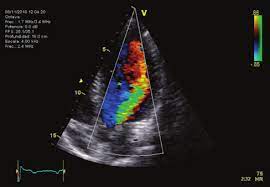

Otro hallazgo clínico importante en la regurgitación aórtica aguda es el fenómeno de pre-cierre de la válvula mitral. Debido al rápido aumento en la presión diastólica del ventrículo izquierdo, la válvula mitral puede cerrarse prematuramente, incluso antes de que se inicie la sístole del ventrículo izquierdo. Este cierre prematuro reduce o incluso anula el primer tono cardíaco (S1), haciéndolo disminuir o ser inaudible durante la auscultación. La identificación de este fenómeno es crucial y puede ser detectada fácilmente mediante ecocardiografía.

El pre-cierre de la válvula mitral, observable en la ecocardiografía, se considera una indicación para una intervención quirúrgica urgente. La imagen ecocardiográfica puede mostrar el cierre anormal de la válvula mitral y la alta presión diastólica del ventrículo izquierdo, confirmando la necesidad de una corrección quirúrgica inmediata para abordar la regurgitación aórtica aguda y aliviar el estrés hemodinámico severo sobre el corazón.

La ecocardiografía se destaca como una herramienta diagnóstica clave, ya que permite evaluar las características principales de la enfermedad. Este método puede determinar si la lesión afecta la raíz aórtica proximal y qué patología valvular está presente. Dado que la severidad de la regurgitación aórtica puede progresar con el tiempo, es crucial realizar evaluaciones anuales del tamaño y la función del ventrículo izquierdo para definir el momento adecuado para la sustitución valvular en casos de regurgitación severa. La guía de valvulopatías de la ACC/AHA de 2020 establece criterios específicos para evaluar la severidad de la regurgitación aórtica.